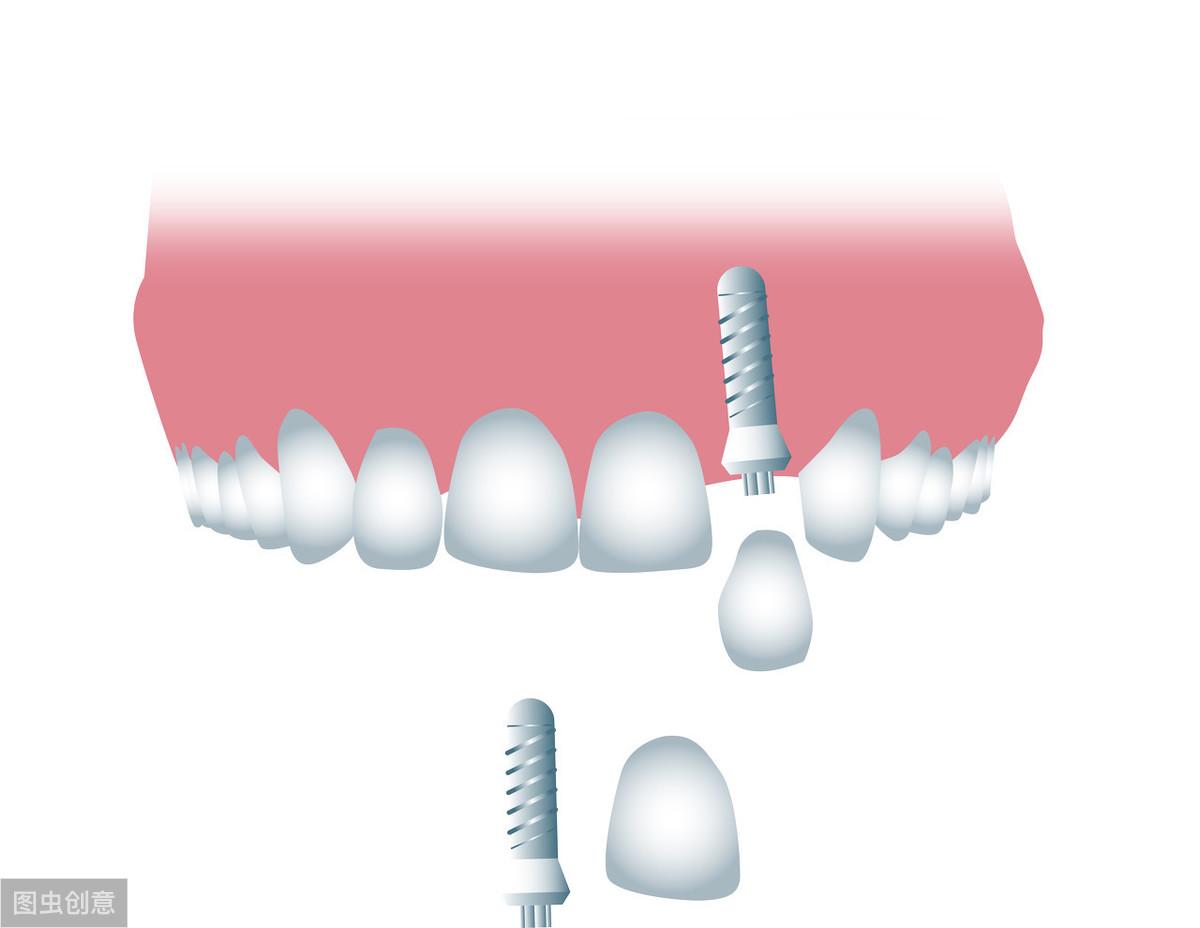

牙齒種植術(shù)是目前好的缺失牙齒修復(fù)技術(shù)之一,因?yàn)樗姆N植技術(shù)是通過(guò)手術(shù)將種植體植入到牙槽骨里,獲得了骨組織的固位支持,所以種植牙齒的穩(wěn)定性、性和使用年限都高,因此,種植牙從發(fā)展到現(xiàn)在也獲得了醫(yī)學(xué)界專家廣泛的認(rèn)可和大量有需要患者的喜愛(ài)。

一、種植牙的性怎樣?牙齒種植是一種系數(shù)很高的修復(fù)方法,他的創(chuàng)傷很小,在不損傷附近牙齒的情況下只針對(duì)缺失的牙齒做修復(fù);且牙齒種植術(shù)發(fā)展了40多年,經(jīng)過(guò)不斷的科技進(jìn)步和技術(shù)更新,現(xiàn)在的牙齒種植術(shù)已經(jīng)成熟了,所以無(wú)需過(guò)度擔(dān)心問(wèn)題。

二、種植牙適合什么年齡階段?因?yàn)榉N植牙齒需要把種植體植入到牙槽骨,所以需要骨骼維持在一個(gè)相對(duì)平穩(wěn)的狀態(tài),18歲左右人類的骨骼發(fā)育基本上就可以發(fā)育成熟,所以18歲以后就可以進(jìn)行牙齒種植了,種植年齡上限也沒(méi)有過(guò)高要求,即使是七八十歲的老人,只要身體健康符合標(biāo)準(zhǔn),也是可以進(jìn)行牙齒種植的;但是即便沒(méi)有年齡限制,種植牙也不是任何人都可以種,骨密度不符合種植標(biāo)準(zhǔn)、高血壓、心臟病、糖尿病和有出血性疾病的患者都不適合馬上進(jìn)行牙齒種植,如有植牙需求應(yīng)該等到病情穩(wěn)定或者采用其他替換方法。